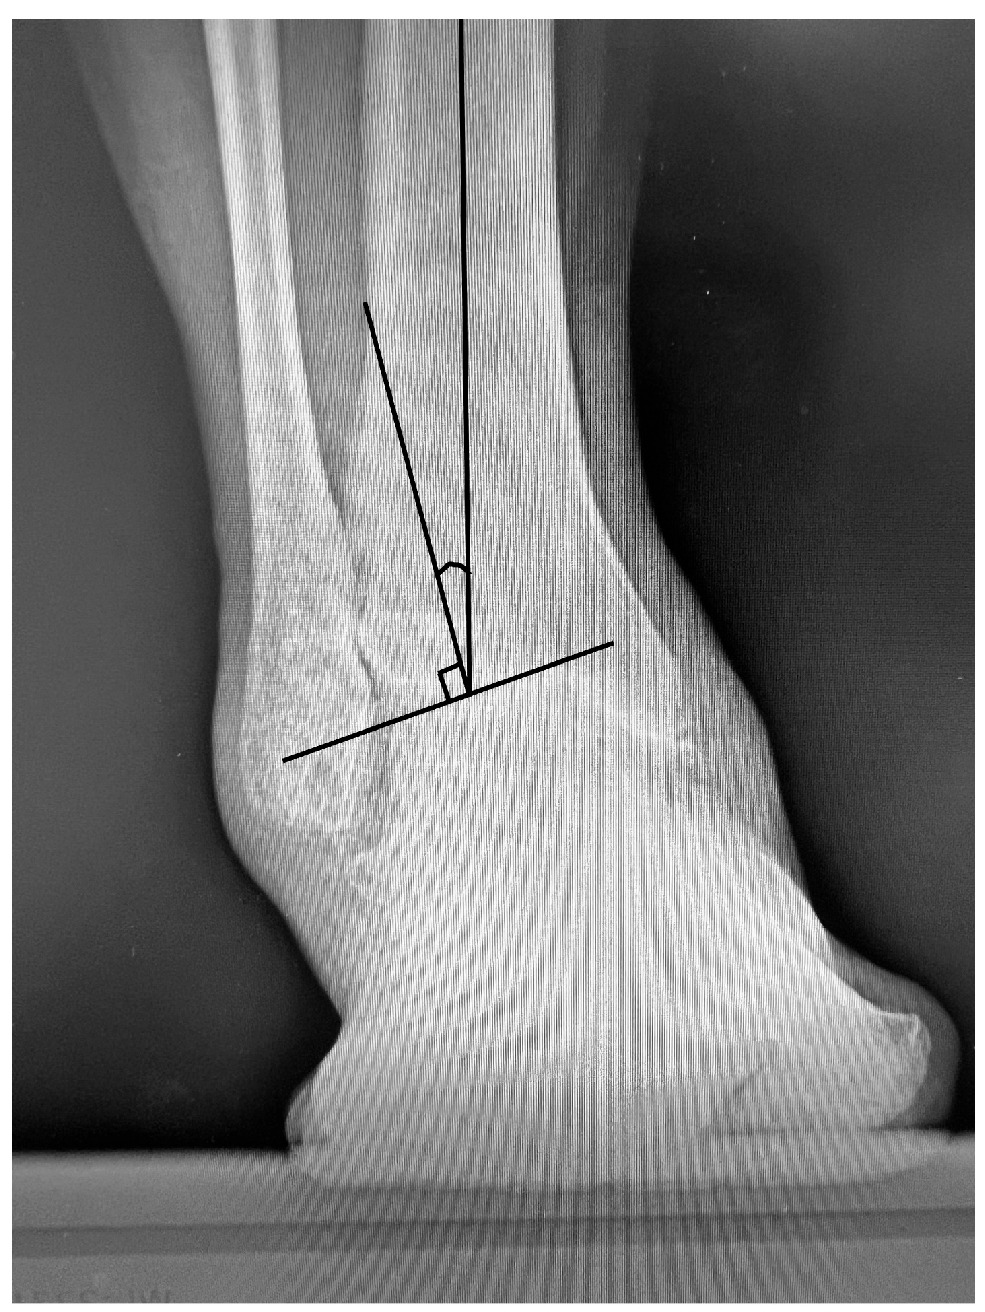

Figure 2.

Anteroposterior weight-bearing radiograph demonstrating measurement of the tibiotalar angle (TTA). The TTA is defined as the angle formed between the anatomical axis of the tibia and the perpendicular line to the articular surface of the talar dome preoperatively or the talar component postoperatively.

Radiographic assessments were performed on weight-bearing anteroposterior radiographs of the tibiotalar joint preoperatively, 3 months postoperatively, and at the latest follow-up visit. All radiographic measurements were performed by a single orthopedic surgeon who was not blinded to the clinical data. Coronal angulation of the tibiotalar joint was assessed using the tibiotalar angle (TTA;

Figure 2) on weight-bearing anteroposterior radiographs both preoperatively and postoperatively.